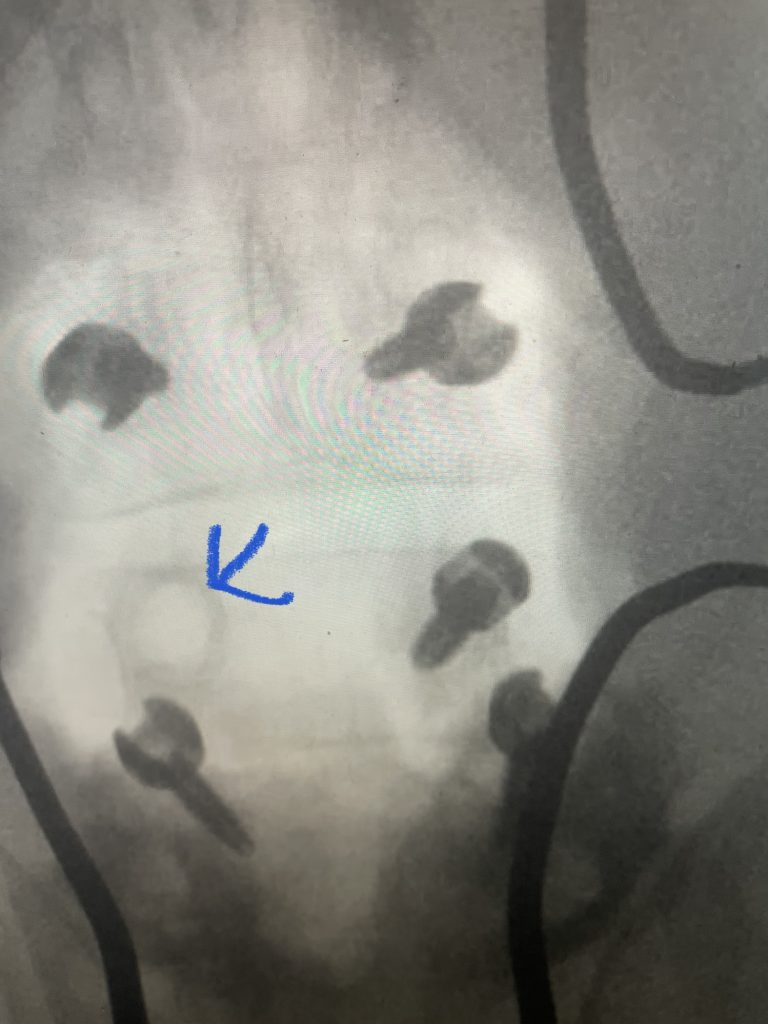

Fig 7: Intraoperative fluoroscopic AP image of the new construct from L3-5. Note the very large lucency around prior L4 screw